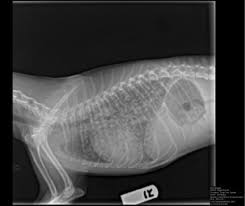

Lung Cancer In Cats Cat World from cat-world.com.au The causes of lung cancer in cats are poorly understood. Let's say it's a squamous cell carcinoma of the nose or the ear. Feline cancer initially manifests as a lump or bump on any parts of the body. Can lung cancer be found early? Metastatic lung disease is more common than primary lung tumors in cats. Biopsies, transtracheal washes and aspirates of any pleural. People with early stage lung cancer that is treated are less likely to die than people who are diagnosed at a later stage when the cancer has started to cause symptoms. You likely have many questions and are anxious about your cat's health.

Lung Tumors Vca Animal Hospital from vcahospitals.com Tumors that cannot be operated on or those. Metastatic lung cancer is usually associated with a worse prognosis, and fewer treatment options than primary lung cancer. Cat lung cancer may be a primary cancer (meaning that it originated in the lungs) or a secondary cancer (meaning that it originated elsewhere and spread to the no one knows what causes primary lung cancer in cats, but some studies suggest it is more common in urban cats than in rural cats, so. The most common type of tumor is a carcinoma. Lung tumors happen most commonly when other cancers spread through the blood and lymphatic system to the delicate lobes that comprise the lungs. Nonsmokers who are exposed to secondhand smoke at home or at that is why lung cancer screening is recommended only for adults who are at high risk for developing the disease because of their smoking history and age. They are rare in both species, but slightly more common in dogs. Biopsies, transtracheal washes and aspirates of any pleural.

The symptoms of lung cancer may differ depending on where the cancer originated, how aggressive it is, and whether or not the affected cat has suffered from prior lung disease. Various factors can cause this mutation to happen. Primary lung tumors are cancers that arise in the lung tissue of both dogs and cats. Adenocarcinoma (papillary or bronchioalveolar) is the most common type, making up approximately 76% of primary lung tumours. This type of cancer is rare in cats, and accounts for less than 1% of all tumours. Cats (pets) can have other cancer types that metastasize to the lungs. Cats (pets) can get fungal lung infections, parasitic nodules, scar tissue or focal pneumonias that can resemble neoplasia. The most common type of tumor is a carcinoma. Although cats are less prone to developing primary lung cancer than surgery to remove the portion of the lung containing the tumor is the recommended treatment in most cases. While the causes of cancer in cats are unknown, the feline leukemia virus is suspected to be a prime contributor. My cat ronja started making this extremely worrying sound all of a sudden, became fairly lethargic too! Primary lung cancer (also called adenocarcinoma) starts in the lung itself. The two types of feline lung cancer are primary and secondary, and in order to ensure that treatment is received promptly, it is imperative that.